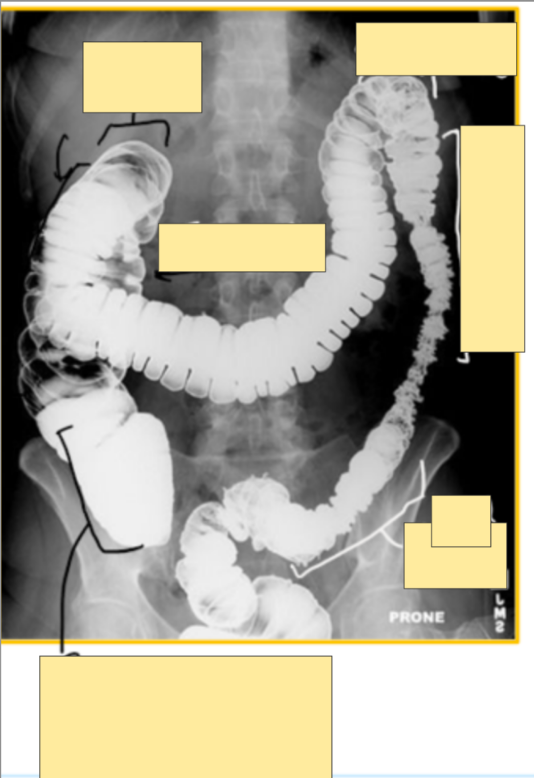

Q

Label the parts of the colon/ large intestine on the X-ray

A

where does cecum reside?

next to right illiac fossa, before becoming the ascending colon